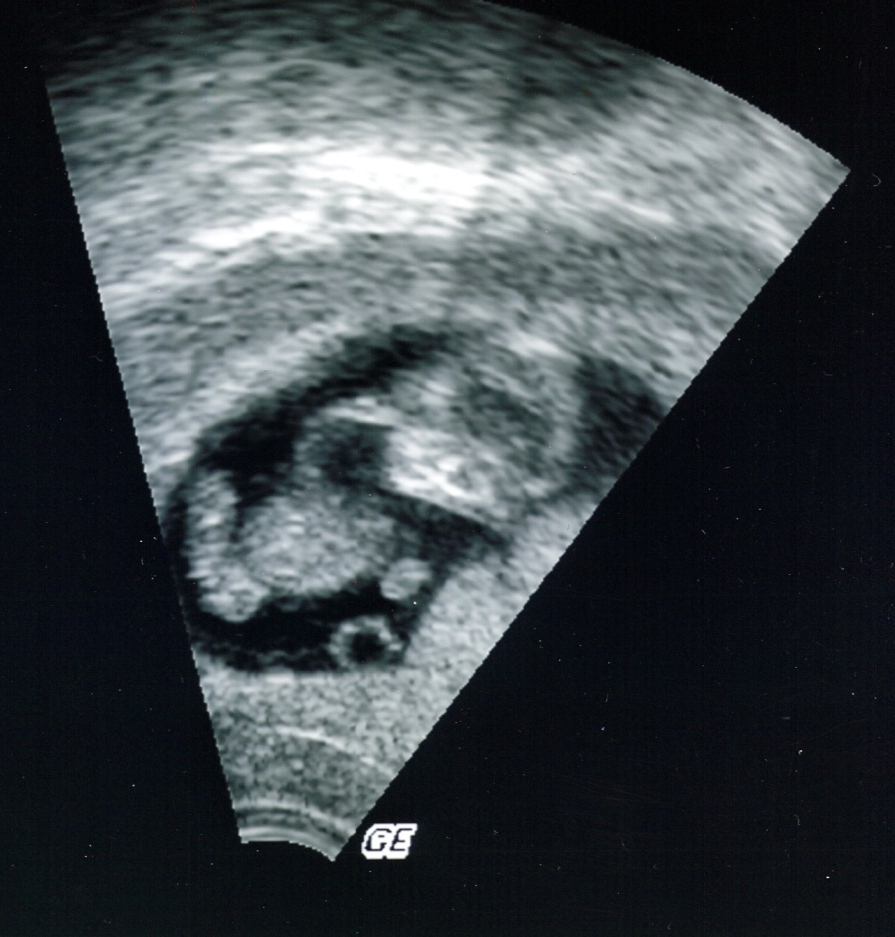

mein US am Freitag war toll. Es sieht alles gut aus. Arme, Beine sind dran und die Augen, der Mund und Nase waren auch schon zu sehen. Und dann hat es sich noch bewegt. Das war soooo schön. Anbei ein Foto in Frontansicht, es hat sich ein Auge zugehalten. :lol:

11+0.jpg